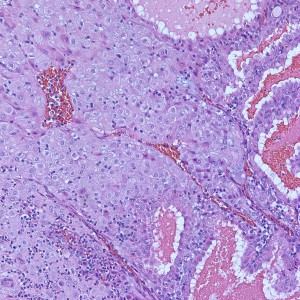

At low power, the majority of the specimen consists of decidua (square) and gestational-type endometrium (circle).

At low power we see throughout the specimen that numerous enlarged hydropic chorionic villi are present (circles).